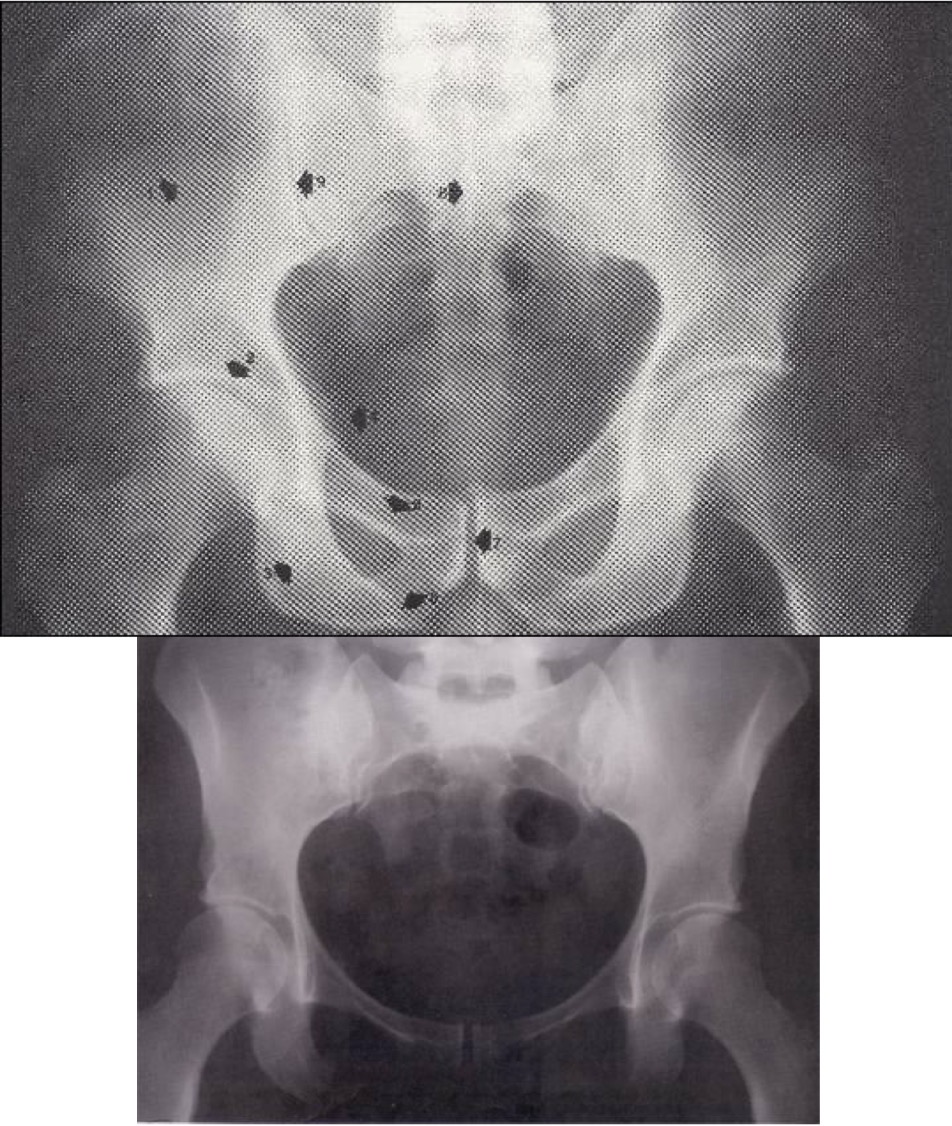

Tyrimas atliktas pacientui gulint. Matomos dubens kaulinės struktūros, juosmeninė stuburo dalis, kryžmeniniai klubų ir klubų sąnariai.

Vyro dubuo yra aukštesnis ir siauresnis, angulus infrapubicus mažesnis, foramen obturatorium vertikalesnė, viršutinė dubens atvara siauresnė.